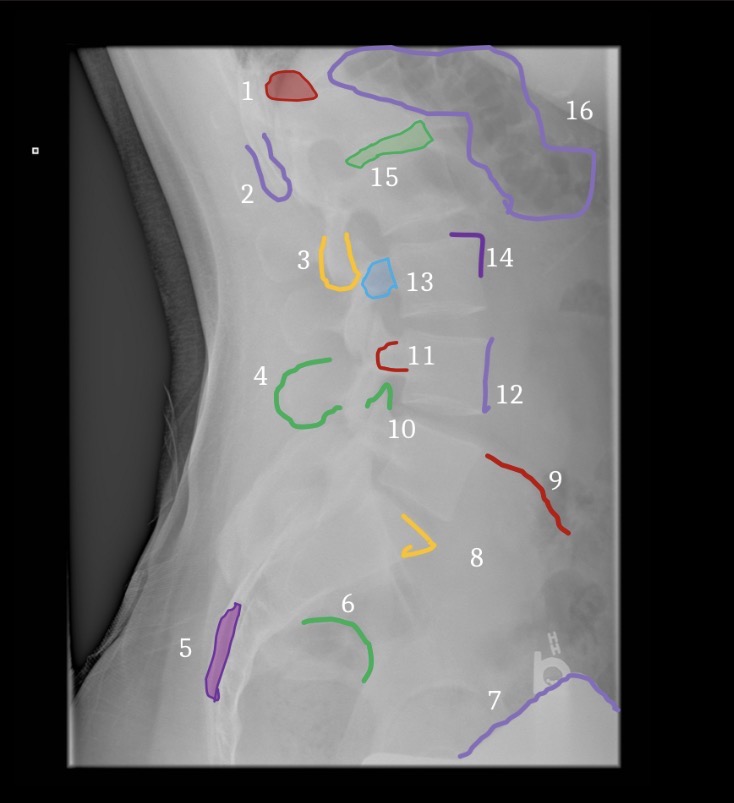

Pedicle

Eye (1)

Transverse process

Nose (6)

Superior articular process

Ear (2)

Inferior articular process

Front leg (5)

Par interarticularis

Neck (3)

Lamina

Body (4)

1

Right ilium

2

Left ilium

3

Right sacral ala

4

Left sacral ala